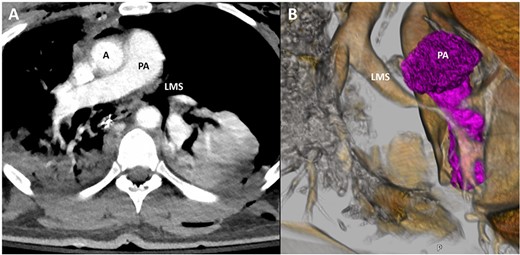

A 28-year-old male hydraulic machinist suffered a mechanical crush injury primarily localized to his left thoracic cavity. He arrived at an outside hospital in respiratory distress with absent breath sounds noted within the left chest. He underwent emergent left-sided tube thoracostomy. Post-placement chest X-ray demonstrated persistent pneumothorax with midline shift, and a second chest tube was subsequently placed. Due to the nature of the injury with associated suspicion of a bronchial injury, the patient was intubated with a double lumen endotracheal tube and was placed on single right lung ventilation. Bronchoscopy at the outside hospital confirmed a left bronchial tear just distal to the carina. A computed tomography (CT) scan demonstrated bilateral pulmonary contusions, pneumomediastinum and a persistent large left hydropneumothorax (Fig. 1). Concurrent injuries also included a right radius and ulnar fracture. He was transferred to our Level 1 trauma, tertiary referral hospital’s surgical intensive care unit for escalation of care.

Representative image of axial slice of CT scan (A) and coronal 3D reconstruction (B) demonstrating narrowing of LMS secondary to bronchial injury; A, aorta; PA, pulmonary artery; LMS, left main stem.